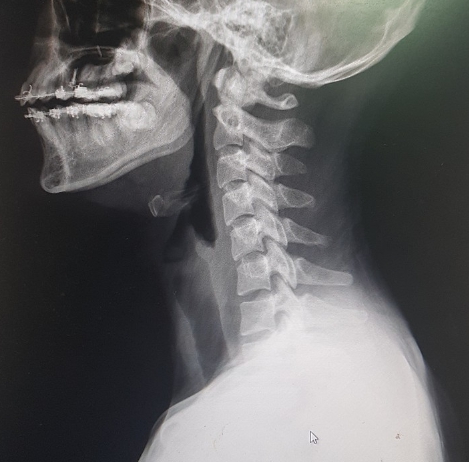

목견인기 사용 시 고려사항 및 추천

안녕하세요. 자세교정 전문 척추닥터입니다. 오늘은 목견인기 사용 시 고려사항 및 추천 에 관한 정보를 전...

목견인기 왜 잘 골라야 할까?

현대인들 대부분 거북목을 앓고 있지만 목견인기를 잘못 쓰게 된다면 오히려 독이 될 수 있으므로 꼭 거북 ...